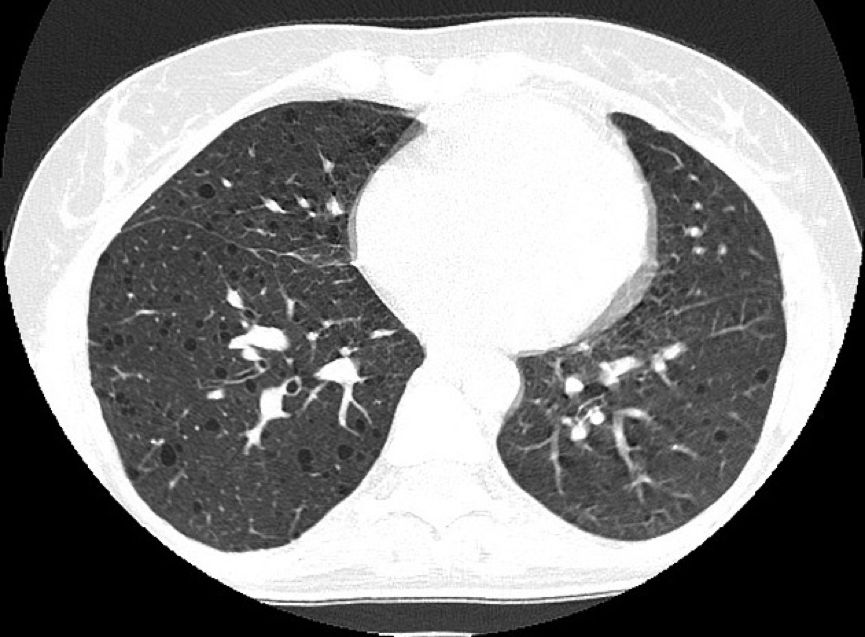

病例1:患者女性,45岁,呼吸短促,有反复气胸的病史。

常规CT表现为两肺密度减低,体积增大,呈肺气肿样改变。HRCT对本病的早期诊断及病情发展的监测有重要意义,其特征性改变为两肺广泛弥漫性分布的薄壁小囊状病变,两侧对称,无上中下肺野的区别,也无中央性与周围性的分布差异。囊腔直径为2~30 mm,大多数直径小于10 mm,囊壁厚度多小于2 mm。